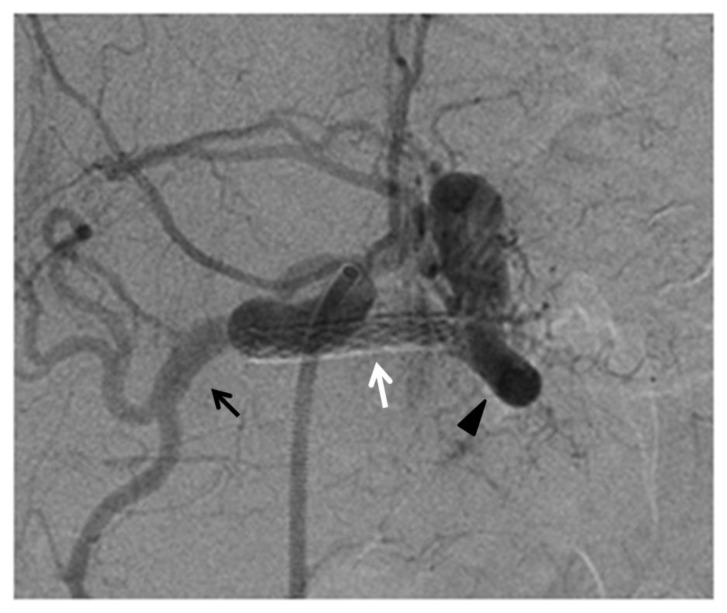

Figure 3.

76-year-old man post deployment of the covered stent in the splenic artery.

FINDINGS: angiography demonstrating the correct position of the covered stent (white arrow) with preservation of flow in the splenic artery (black arrow head) and absence of contrast medium extravasation and preservation of the patency of hepatic artery (black arrow).

TECHNIQUE: selective celiac axis angiography, in anterior-posterior view, after the deployment of the covered. Siemens AXIOM Artis C-arm. Hand injection 5 cc Omnipaque 350. kVp 64, mAs 10.